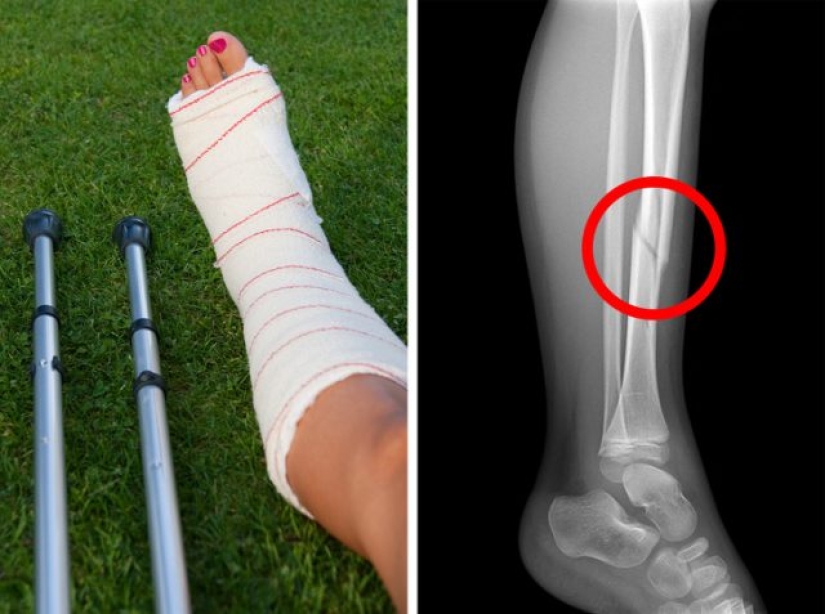

El calcio es esencial para el desarrollo y la salud de los huesos, especialmente durante la infancia. Sin embargo, todos los productos lácteos, o las proteínas animales en general, son ácidos, lo que reduce la ingesta de calcio. Las investigaciones muestran que las mujeres que beben 3 o más vasos de leche al día tienen un mayor riesgo de fracturas.